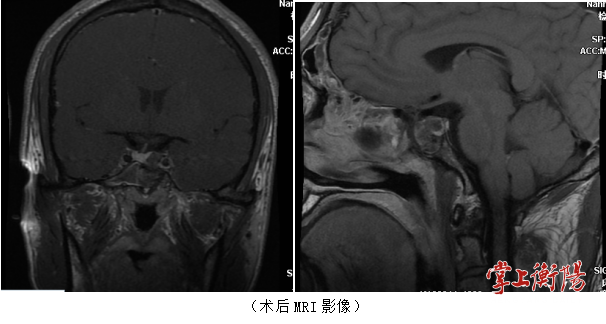

患者入院后,南华医院神经外科积极为患者完善垂体磁共振(MRI)及相关激素检查,考虑垂体生长激素腺瘤可能,经由南华医院神经外科颅底肿瘤亚专科治疗组成员讨论后,建议患者进行手术治疗。经过仔细的术前讨论及准备后,南华医院神经外科颅底肿瘤亚专科团队成功为患者剜除了垂体腺瘤,术后第二天患者便下床自主活动,目前患者已无明显不适,顺利出院。